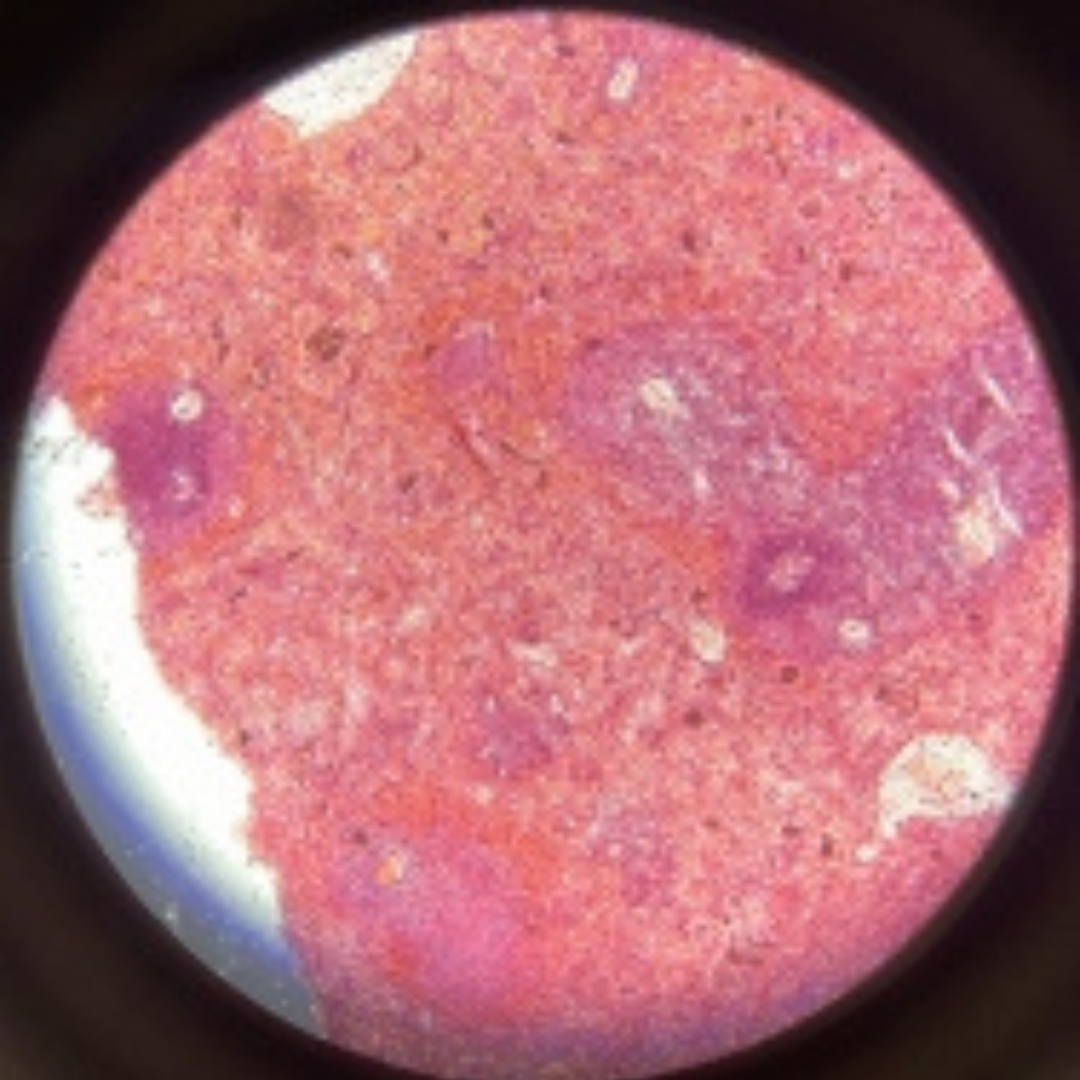

Blood

2

New cards

Blood

3

New cards

Blood

4

New cards

Blood